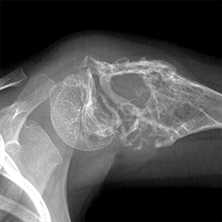

- Деструкция с «разъеданием» костной структуры на рентгенограммах выглядит как дефект - «дырка», такой вариант метастазирования называют остеолитическим, что буквально означает «съеденная кость».

- При утолщении кости за счёт опухоли рентгенограмма выявляет «плюс ткань», тогда говорят об остеопластическом метастазировании.

- Как правило, у больного встречаются оба вида метастазов с превалированием одного из вариантов, в большинстве случаев остеолитического.